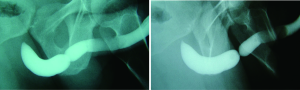

Patient positioning during retrograde urethrogram is critical. The patient should be in an oblique position (35-45 degrees) to maximize visualization of the bulbar urethra. Proper positioning can be confirmed by a closed downward oriented obturator foramen. Such a position ensures that the majority of the urethra is parallel to the radiographic film. Improper positioning will place the urethra at an angle relative to the film, and result in underestimation of stricture length (5). The penis should be placed on stretch in order to maximize complete assessment of the urethra. The use of anesthetic-impregnated lubrication can obscure the image, induce edema, and provide questionable benefit to patient comfort (6). Contrast should be visualized through the stricture and the membranous urethra to allow imaging of the urethra proximal to the stricture, in order to ensure that the full extent of urethral pathology is visualized. The importance of patient positioning is demonstrated in Figure 1.